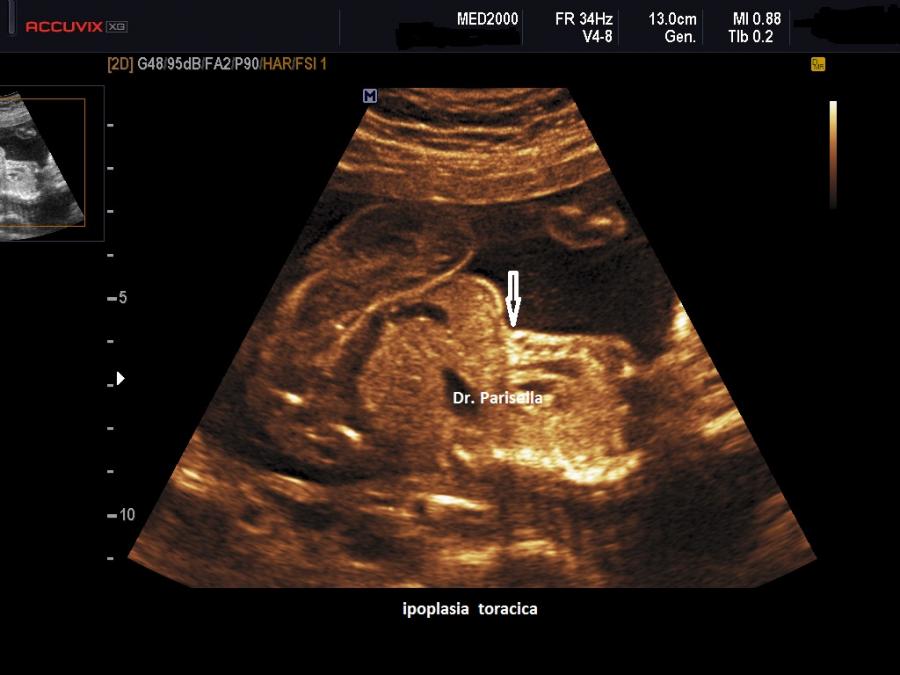

La forma grave (perinatale, infantile) è simile all'osteogenesi imperfetta tipo II con severo accorciamento degli arti (specie femore ed omero) la cui diafisi appare ricurva, ipoplasia toracica grave, ipomineralizzazione diffusa ad eccezione delle clavicole, idrope (nelle forme ad insorgenza precoce), polidramnios; incostantemente si hanno coste sottili e sedi di fratture.

MICROMELIA SEVERA, IPOPLASIA TORACICA SEVERA, IPOMINERALIZZAZIONE ESTREMA TRANNE LE CLAVICOLE, IDROPE (evidente principalmente nei casi a riscontro precoce), DEFORMAZIONE DELLA VOLTA CRANICA ALLA COMPRESSIONE IMPRESSA DALLA SONDA.